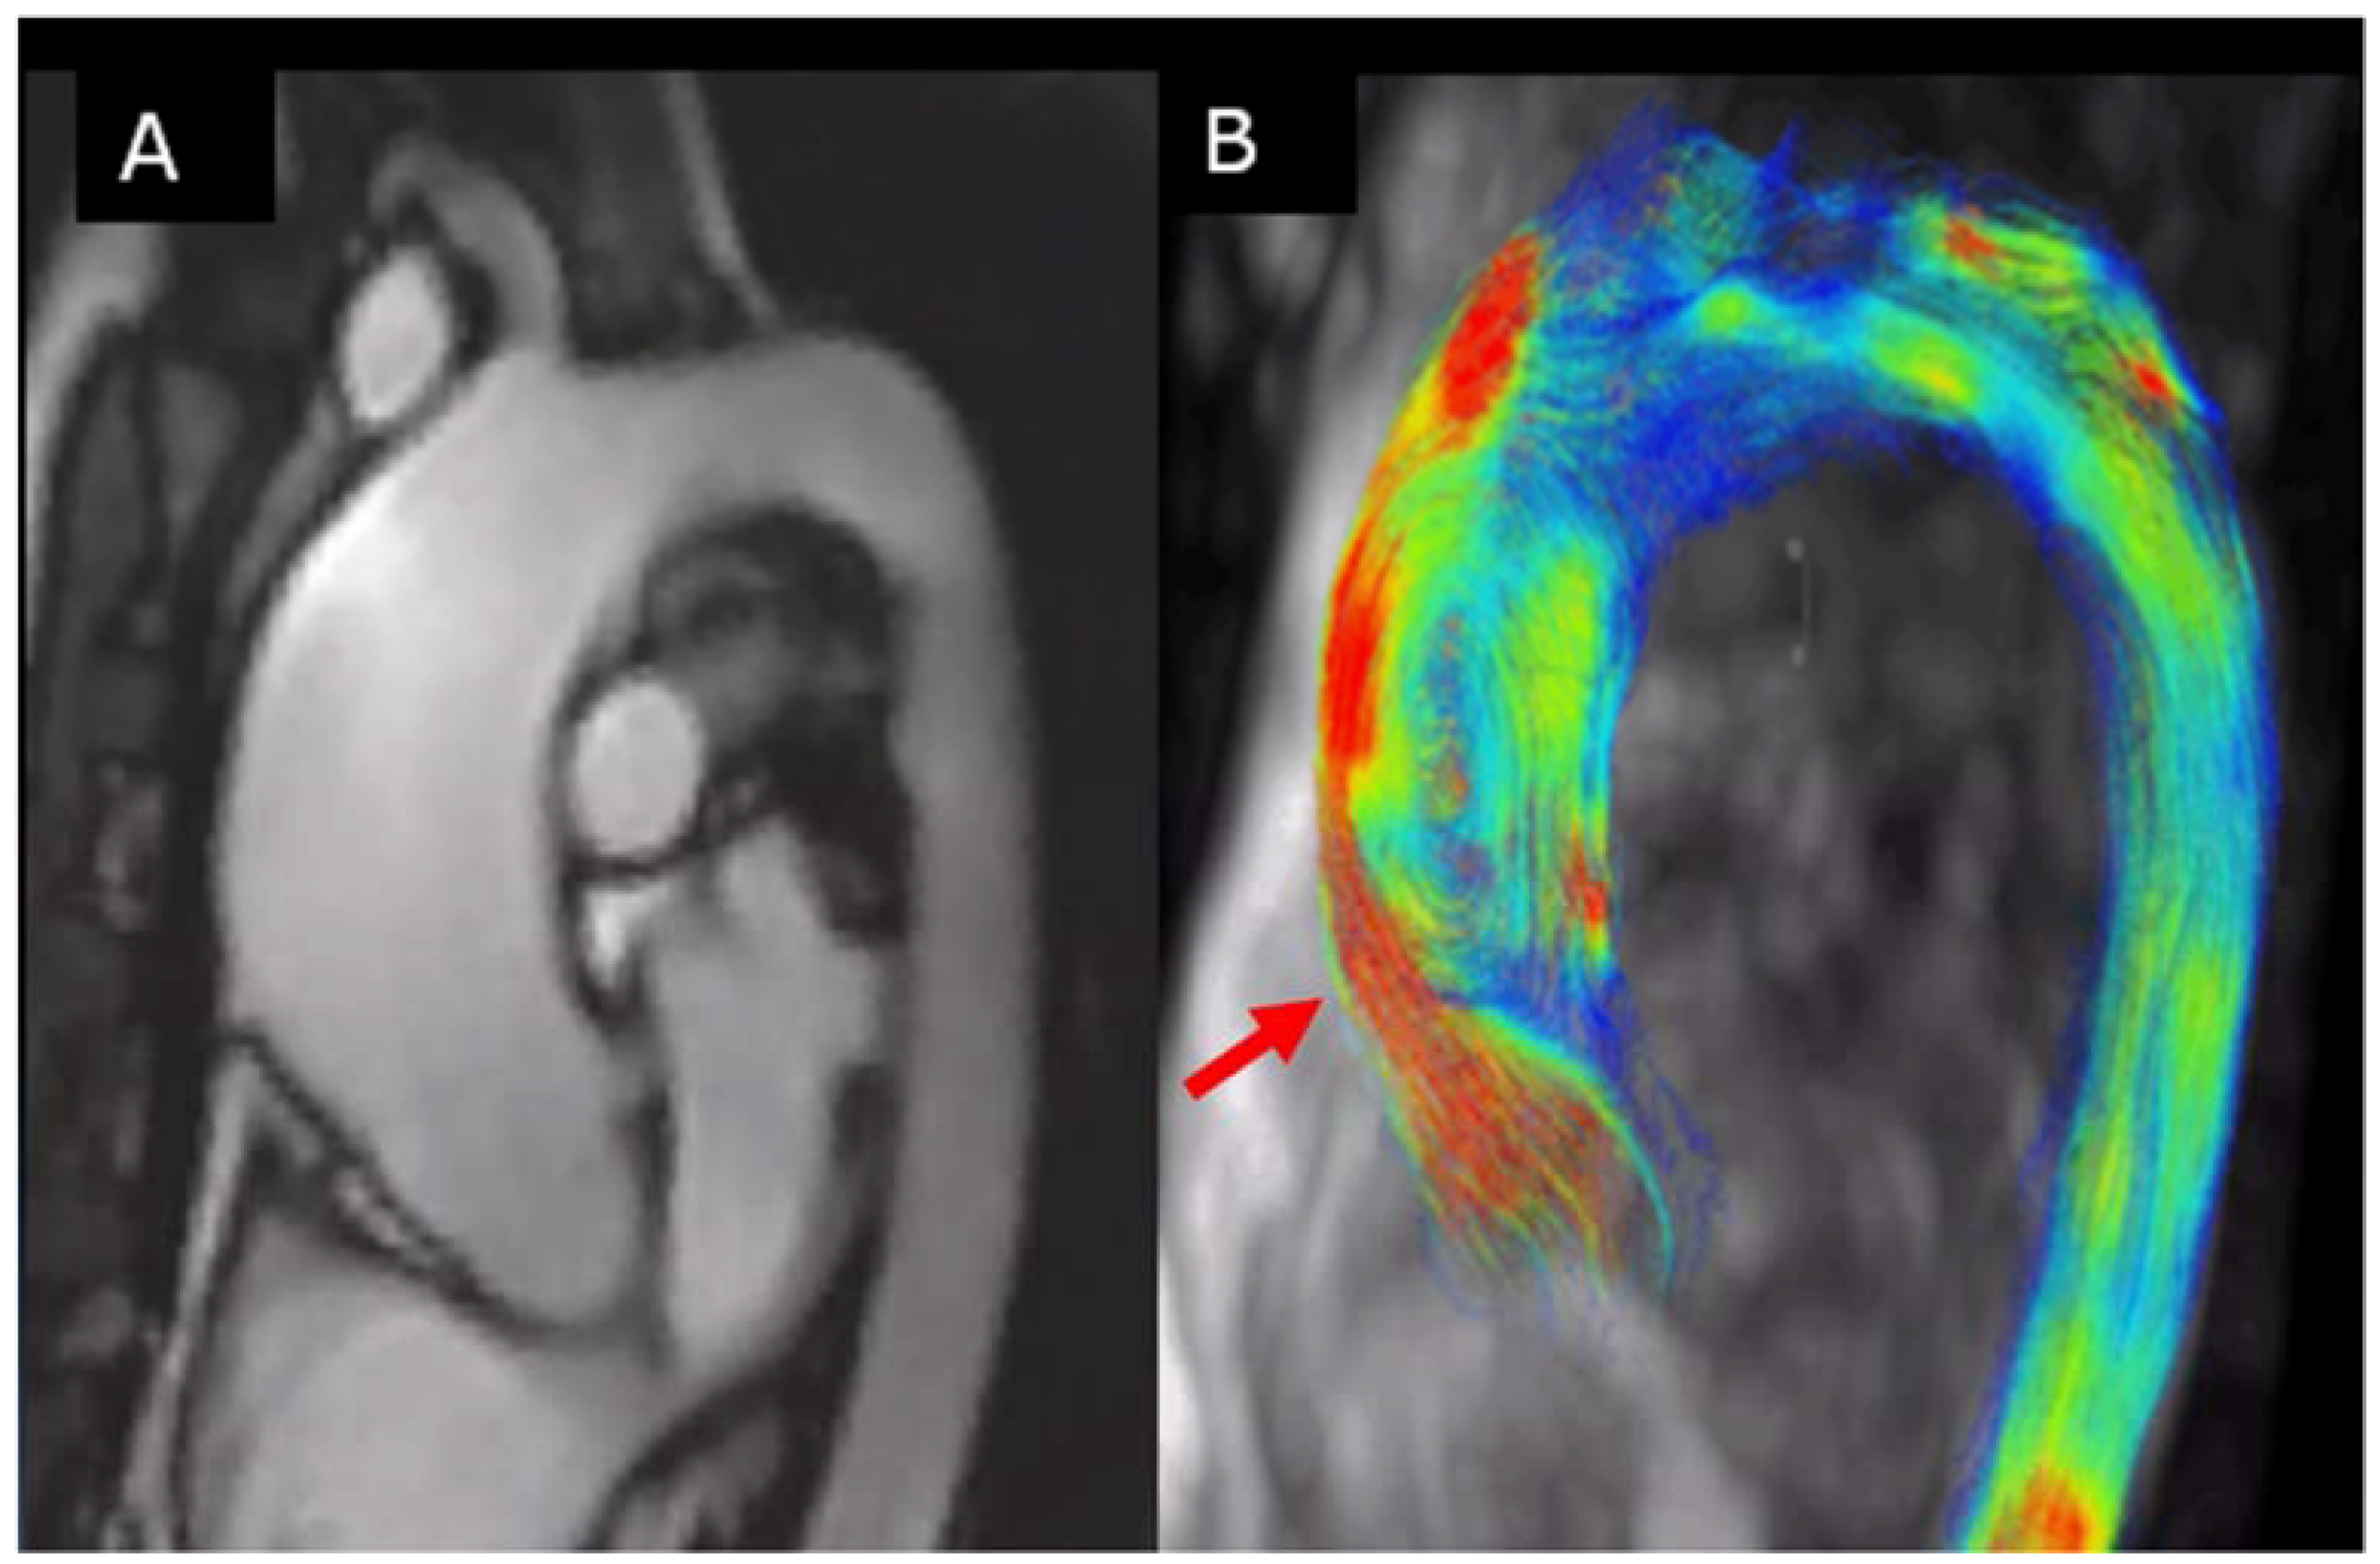

6.2. Aortic Flow Hemodynamic Parameters

- Rodriguez-Palomares, J.F.; Dux-Santoy, L.; Guala, A.; Kale, R.; Maldonado, G.; Teixido-Tura, G.; Galian, L.; Huguet, M.; Valente, F.; Gutierrez, L.; et al. Aortic flow patterns and wall shear stress maps by 4D-flow cardiovascular magnetic resonance in the assessment of aortic dilatation in bicuspid aortic valve disease. J. Cardiovasc. Magn. Reson. 2018, 20, 28. [Google Scholar] [CrossRef] [PubMed]

- Bissell, M.M.; Hess, A.T.; Biasiolli, L.; Glaze, S.J.; Loudon, M.; Pitcher, A.; Davis, A.; Prendergast, B.; Markl, M.; Barker, A.J.; et al. Aortic dilation in bicuspid aortic valve disease: Flow pattern is a major contributor and differs with valve fusion type. Circ. Cardiovasc. Imaging 2013, 6, 499–507. [Google Scholar] [CrossRef] [PubMed]

- Dux-Santoy, L.; Guala, A.; Teixidó-Turà, G.; Ruiz-Muñoz, A.; Maldonado, G.; Villalva, N.; Galian, L.; Valente, F.; Gutiérrez, L.; González-Alujas, T.; et al. Increased rotational flow in the proximal aortic arch is associated with its dilation in bicuspid aortic valve disease. Eur. Heart J. Cardiovasc. Imaging 2019, 20, 1407–1417. [Google Scholar] [CrossRef] [PubMed]

- Mahadevia, R.; Barker, A.J.; Schnell, S.; Entezari, P.; Kansal, P.; Fedak, P.W.M.; Malaisrie, S.C.; McCarthy, P.; Collins, J.; Carr, J.; et al. Bicuspid aortic cusp fusion morphology alters aortic three-dimensional outflow patterns, wall shear stress, and expression of aortopathy. Circulation 2014, 129, 673–682. [Google Scholar] [CrossRef] [PubMed]

- Guzzardi, D.G.; Barker, A.J.; van Ooij, P.; Malaisrie, S.C.; Puthumana, J.J.; Belke, D.D.; Mewhort, H.E.M.; Svystonyuk, D.A.; Kang, S.; Verma, S.; et al. Valve-Related Hemodynamics Mediate Human Bicuspid Aortopathy: Insights From Wall Shear Stress Mapping. J. Am. Coll. Cardiol. 2015, 66, 892–900. [Google Scholar] [CrossRef] [PubMed]

- Guala, A.; Dux-Santoy, L.; Teixido-Tura, G.; Ruiz-Muñoz, A.; Laura Galian-Gay, M.L.; Servato, F.V.; Laura Gutiérrez, T.G.-A.; Johnson, K.M. Wall shear stress predicts aortic dilation in patients with bicuspid aortic valve. JACC Cardiovasc. Imaging 2021, in press. [Google Scholar] [CrossRef] [PubMed]